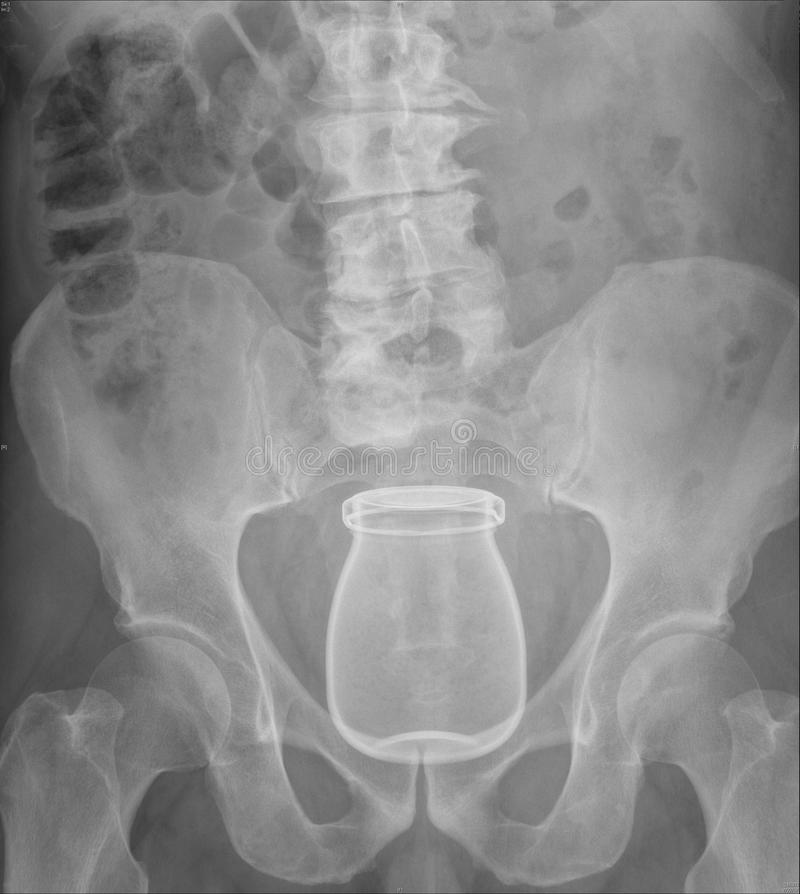

tis maar een bierflesje, wacht maarrrrr...bijna nieuwjaarEven eerlijk, jij kan zo’n fles ook wel hebben toch?

Wat zit jij nou weer te brabbelen?tis maar een bierflesje, wacht maarrrrr...bijna nieuwjaar![]()